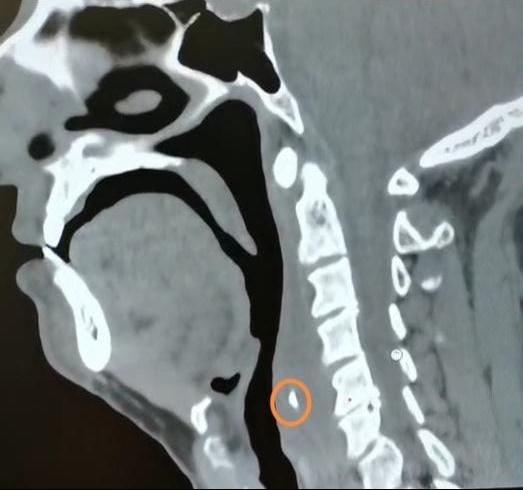

近日,家住饶河的王先生在家吃“嘎牙子”鱼时,不小心被鱼刺卡住了喉咙,但王先生并没有当回事,喝了几口醋,吞了馒头想把刺“推”下去,结果却不如人意,喉咙越来越疼了。王先生又用了几天消炎药后仍是疼痛难忍,于是去了当地医院,做颈部CT检查,结果显示鱼刺完全没入软组织内。经多方打听,王先生来到哈医大四院就诊。

【 鱼刺卡喉|鱼刺卡喉用“老土方”?专家:不科学且危险!】经过详细检查,哈医大四院耳鼻咽喉头颈外科主任周彬为王先生进行急诊全麻下支撑喉镜下下咽后壁切开异物取出术。术中可见咽后壁粘膜光滑,会厌高度偏左侧的咽后壁略隆起。在隆起处以激光纵行切开粘膜及粘膜下组织,脓性液体流出,其内可见一白色鱼刺。完整取出鱼刺,可见其上端呈针尖状,整体呈弧形,边缘锐利光滑,无破损。术后,王先生恢复良好。